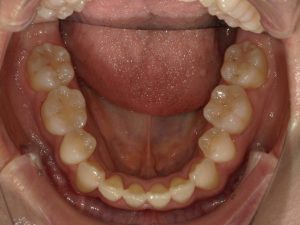

治療前→治療後(下顎)